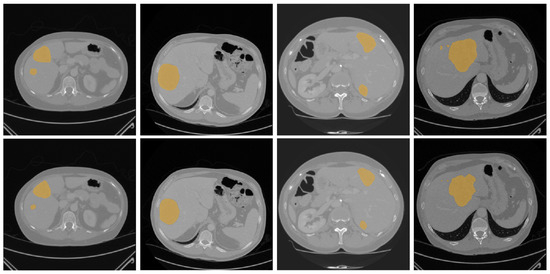

Precise medical image segmentation plays a vital role in disease diagnosis and clinical treatment. Although U-Net-based architectures and their Transformer-enhanced variants have achieved remarkable progress in automatic segmentation tasks, they still face challenges in complex medical imaging scenarios, particularly around simultaneously modeling fine-grained local details and capturing long-range global contextual information, which limits segmentation accuracy and structural consistency. To address these challenges, this paper proposes a novel medical image segmentation framework termed DA-TransResUNet. Built upon a ResUNet backbone, the proposed network integrates residual learning, Transformer-based encoding, and a dual-attention (DA) mechanism in a unified manner. Residual blocks facilitate stable optimization and progressive feature refinement in deep networks, while the Transformer module effectively models long-range dependencies to enhance global context representation. Meanwhile, the proposed DA-Block jointly exploits local and global features as well as spatial and channel-wise dependencies, leading to more discriminative feature representations. Furthermore, embedding DA-Blocks into both the feature embedding stage and skip connections strengthens information interaction between the encoder and decoder, thereby improving overall segmentation performance. Experimental results on the LiTS2017 dataset and Sliver07 dataset demonstrate that the proposed method achieves incremental improvement in liver segmentation. In particular, on the LiTS2017 dataset, DA-TransResUNet achieves a Dice score of 97.39%, a VOE of 5.08%, and an RVD of −0.74%, validating its effectiveness for liver segmentation. Full article

Show Figures

Figure 1